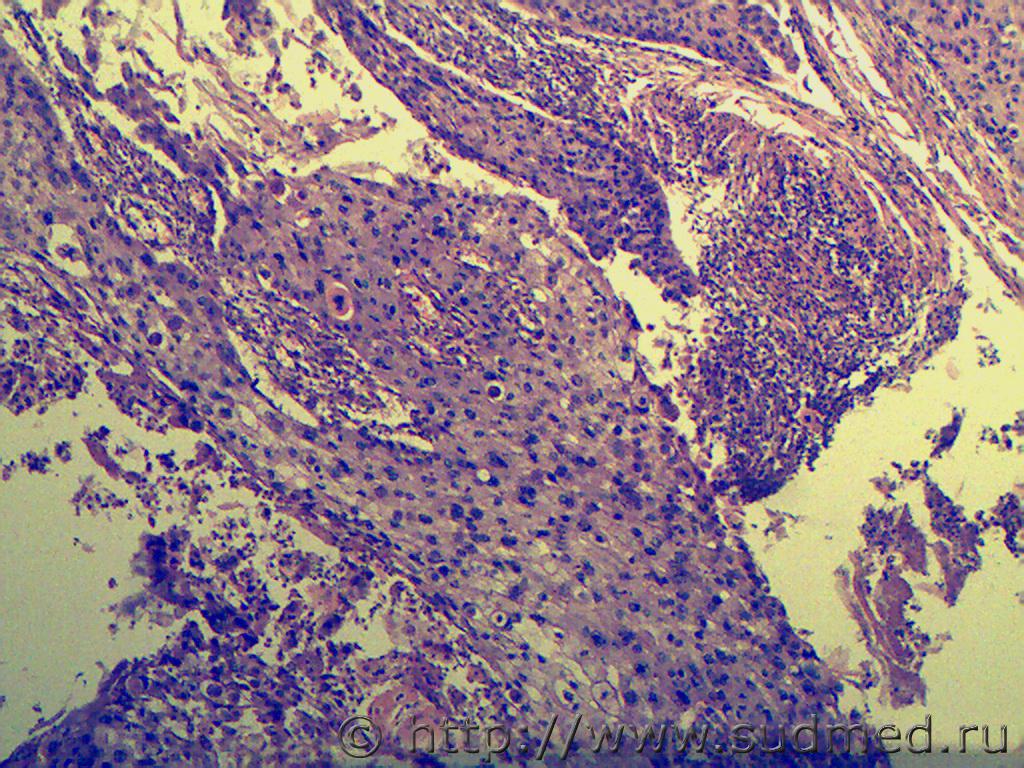

Медик Язва кожи 13.11.2013 - 12:58

Unior В принципе, похоже. Если язва на губе (вообще на л... 13.11.2013 - 13:43

Медик Если голень... то ?

То что? 13.11.2013 - 18:15

Anton То кератоакантома. Однако, онкоморфологов надо. 13.11.2013 - 18:44

Медик кератоакантома.

Мысль была,но здесь клеточный по... 13.11.2013 - 19:44

Unior Нет, ну, чё сразу кошмары рисовать то, может прост... 15.11.2013 - 12:22

Медик Когда-то один патанатом, говорил, что для него одн... 15.11.2013 - 19:38

Smeks1 Уважаемые коллеги, мое мнение - плоскоклеточный, G... 15.11.2013 - 13:10